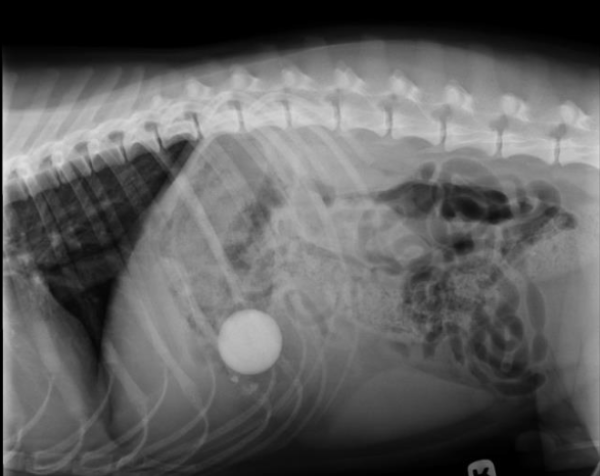

Ellie is a one-year-old, female spayed, Golden Retriever presenting for an endoscopic gastrointestinal foreign body removal. Ellie was transferred to Iowa Veterinary Specialty from Waukee-Clive rDVM after owners noticed lethargy and diarrhea for one day. The rDVM provided radiographs, bloodwork, and administered Cerenia, an antiemetic, to manage nausea. There appeared to be a rock present in the stomach on the abdominal radiographic images.

Upon physical exam, Ellie had mild hyperthermia at 102.9 F and a slightly muddy mucous membrane. Her abdomen was tense on palpation indicating that she was likely uncomfortable. She was graded a 1/4 on the pain scale. Ellie had an otherwise unremarkable physical exam. Radiographs and bloodwork were forwarded from the rDVM, limiting the need for further diagnostics. It was recommended to repeat radiographs prior to the endoscopy to ensure the rock had not traveled further into the gastrointestinal tract where the foreign material could not be removed with an endoscope.

Ellie was diagnosed with a gastrointestinal foreign body, suspected to be a rock on radiographs and confirmed/resolved with an endoscope performed by Dr. Bartlett.

There are a variety of treatment options based on the circumstances of the case. In Ellie’s case, radiographs were repeated at Iowa Veterinary Specialty prior to the endoscopy to ensure the rock remained in the stomach. As the rock had not yet passed into the intestines and was minimal risk for damaging tissue if removed endoscopically, that was the treatment plan. Ellie was placed under general anesthesia and an endoscope was used to visualize the stomach and proximal descending duodenum. The rock was found in the stomach, grasped with a wire basket attachment, and removed via the oral cavity.